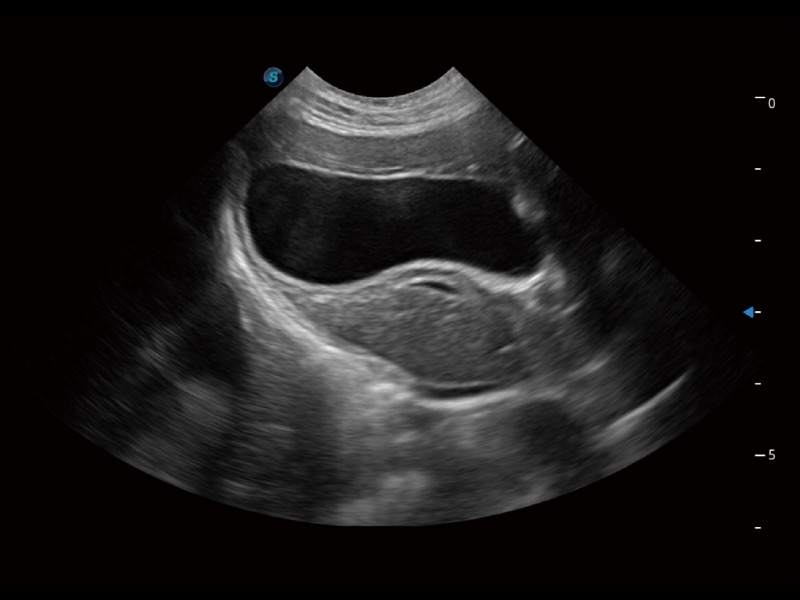

一键自动识别膀胱壁及自动测量膀胱容积,不受膀胱形状和大小的限制,帮助医生快速精准获得测量的数据。

猫、中小型犬及小型异宠动物